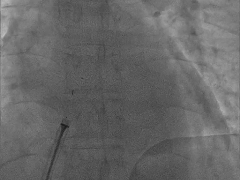

封堵器锁定成型,DSA下牵拉测试,造影确认无残余分流

释放封堵器

剪线并抽出线后解脱钢缆

出院前心脏彩超:

PFO封堵术后,未见异常分流,房间隔膨出瘤,二尖瓣少量反流,三尖瓣少量反流,左室室壁运动正常,左室收缩功能正常,左室舒张功能不全I级。

术后3个月复查心脏彩超:

PFO封堵术后,未见异常分流,二尖瓣少量反流,三尖瓣少量反流,左室室壁运动正常,左室收缩功能正常,左室舒张功能不全I级。